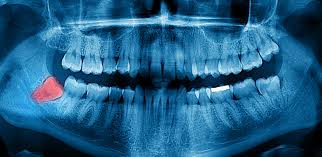

Dentists and oral surgeons typically recommend removal when imaging shows impaction, unfavorable angles, risk to neighboring teeth, or signs of infection.

Advances in 3D dental imaging allow dentists to see the full position and root formation of wisdom teeth with great precision long before any symptoms develop. This has made early intervention and prevention much more effective.